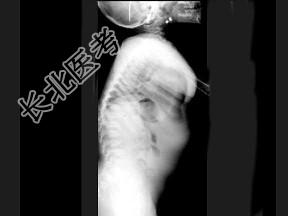

- 单项选择题女,3岁, 身高不增,智力正常, 结合图像,最可能的诊断是 ( )

C、黏多糖贮积症Ⅳ型